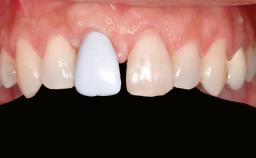

A woman in her mid-fifties was referred by a dental student for dental implant placement. Both posterior segments of the mandible had been edentulous for more than 4 years, the only residual tooth being the right lower first premolar. The patient had used a removable partial denture but was not entirely satisfied with its function. The clinical examination revealed a sharp edentulous ridge in both posterior segments of the mandible, and the patient was told that it would not be possible to insert implants into this thin edentulous ridge without significant augmentation of the alveolar ridge. Her medical history revealed no significant findings and no underlying disease that might have complicated surgical procedures. During the presurgical examination, the patient reported that she was a little apprehensive about bone grafting. After being informed about the surgical procedures and potential postoperative complications, she accepted the proposed surgical plan of bone grafting and subsequent placement of implants.